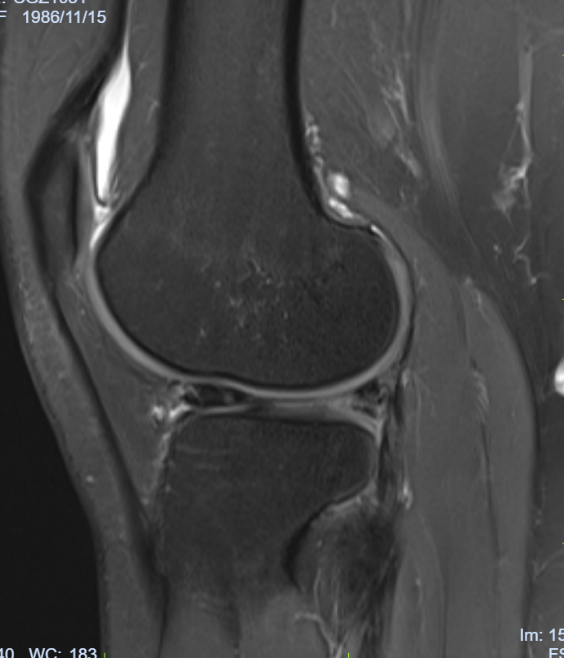

病例七:患者,女,36岁,因“左膝关节疼痛活动受限5天”入院。诊断:左膝外侧半月板撕裂;行左膝关节镜探查+滑膜清理+外侧半月板成形术;手术顺利,术后恢复良好,顺利出院。

左膝外侧半月板撕裂 术前磁共振